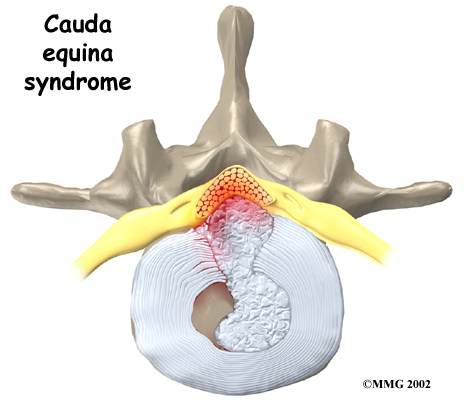

Rarely, symptoms involve changes in bowel and bladder function. A large disc herniation that pushes straight back into the spinal canal can put pressure on the nerves that go to the bowels and bladder. The pressure may cause low back pain, pain running down the back of both legs, and numbness or tingling between the legs in the area you would contact if you were seated on a saddle. The pressure on the nerves can cause a loss of control in the bowels or bladder. This is an emergency. If the pressure isn't relieved, it can lead to permanent paralysis of the bowels and bladder. This condition is called . Doctors recommend immediate surgery to remove pressure from the nerves.